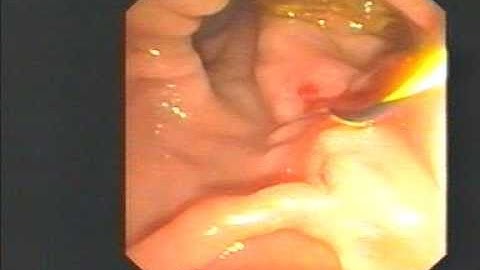

cholangioscopy via sphinctertome